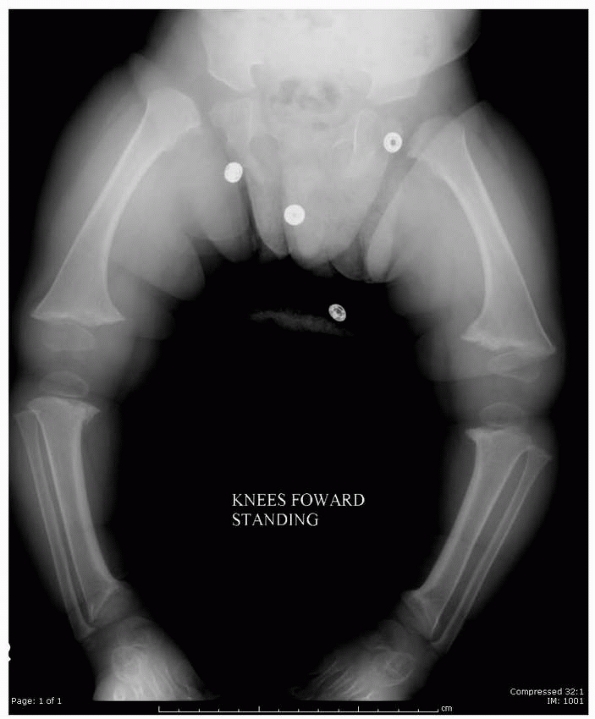

bone diameter and lesions that are associated with marked cortical

thinning are at high risk of fractures and warrant prophylactic

treatment.215,481 Lesions of weight-bearing bones, especially around the hip, need to be addressed (Fig. 6-4).

FIGURE 6-4 Classification system for the treatment of pathologic fractures of the proximal femur associated with bone cysts in children. A.

In type IA, a moderately sized cyst is present in the middle of the femoral neck. There is enough bone in the femoral neck and lateral proximal femur (lateral buttress) to allow fixation with cannulated screws, avoiding the physis, after curettage and bone grafting. B. In type IB, a large cyst is present at the base of the femoral neck. There is enough bone proximally in the femoral neck but there is loss of lateral buttress, so a pediatric hip screw and a side plate should be considered rather than cannulated screws after curettage and bone grafting. C,D. In type II A-B, a large lesion is present in the femoral neck, so there is not enough bone beneath the physis to accept screws. There are two options for treatment of these bone cysts: (i) after curettage and bone grafting, parallel smooth pins across the physis can be used in combination with spica cast; (ii) the patient can be treated in traction until the fracture heals (with subsequent spica cast) followed by curettage and bone grafting. E,F. In type IIIA-B, the physis is closing or closed. The lateral buttress is present in type IIIA hips, so cannulated screws can be used to stabilize the fracture after curettage and bone grafting. In type IIIB hips, the loss of lateral buttress makes it necessary to use a pediatric hip screw and a side plate following curettage and bone grafting. In all types, we recommend spica cast immobilization after surgery. |